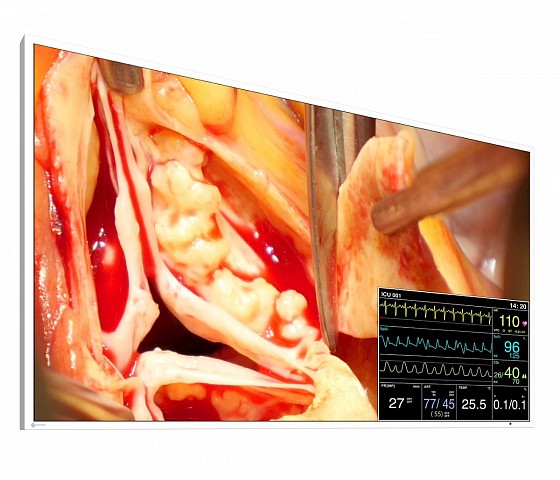

This 49” widescreen monitor is ideally suited for viewing medical images under OR conditions. Numerous input and output signals, image combination capabilities, and gamma models pre-calibrated at the factory enable its use within the widest range of applications. With its fan-free design and water-tight, easy to clean front, the monitor is perfectly suited for sterile hospital environments.

- Flexible image arrangement thanks to the Picture-in-Picture (PiP) and Picture-at-Picture (PaP) functions